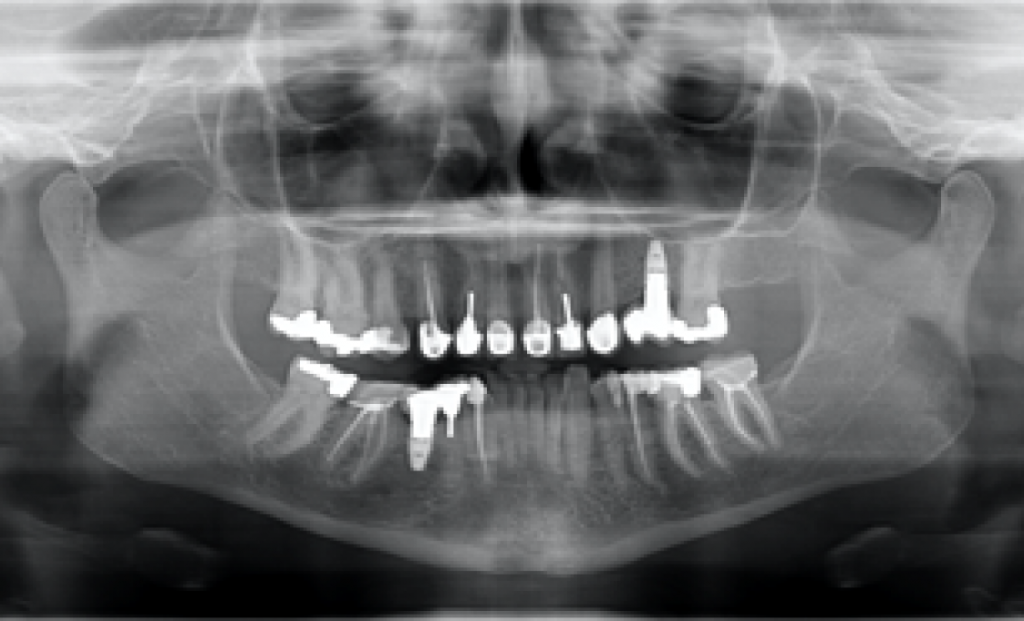

На основе ОПТГ, сделанного после установки или имплантата (рис. 2), стоматолог может выбрать подходящую высоту десневой манжеты для абатмента и направить техника, предоставив рентгеновский снимок и/или спецификацию формирователя десны. Большинство систем имплантатов имеют синхронизированные формы и контуры хирургических абатментов и компонентов протеза.